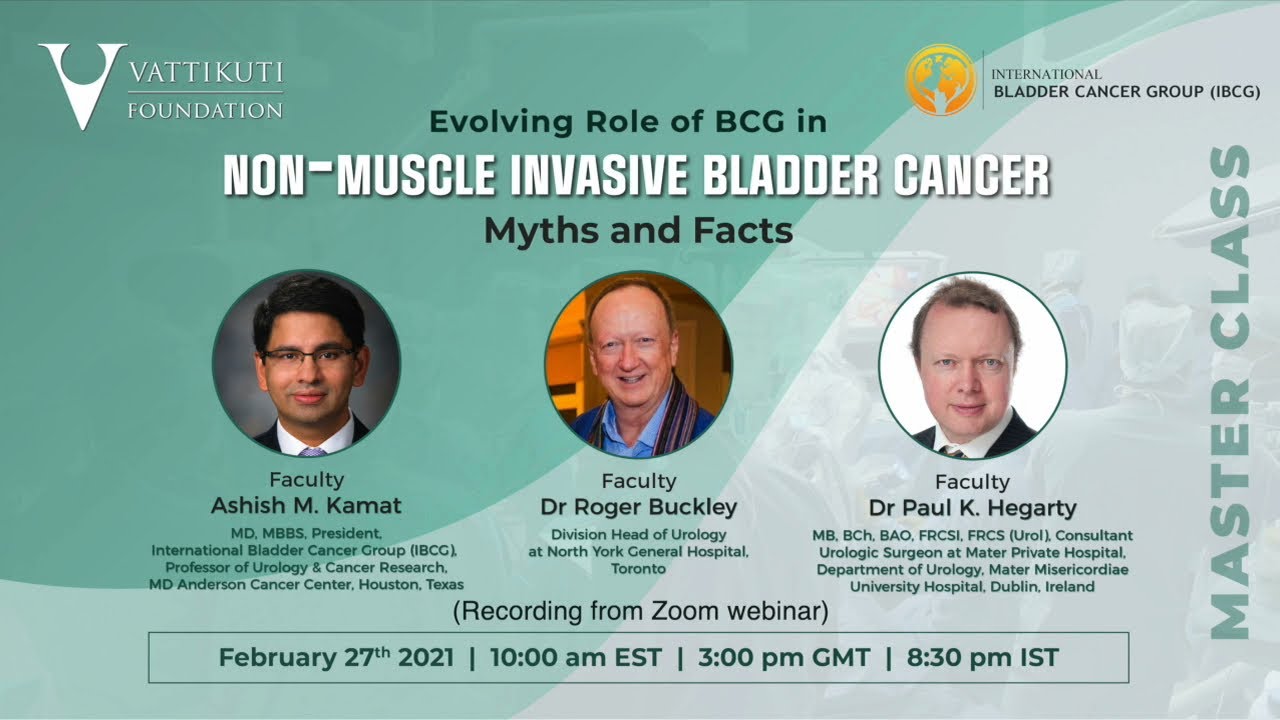

Evolving Role of BCG in Non-Muscle Invasive Bladder Cancer

Masterclass, Urology ';